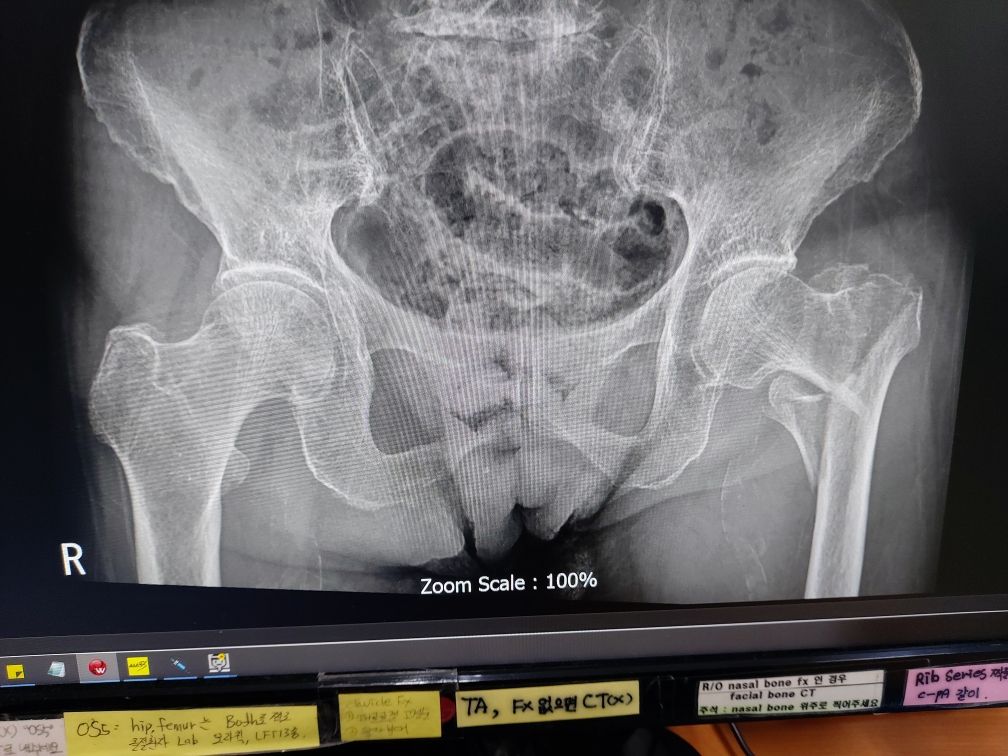

93세 고관절 골절 수술이 꼭 필요할까요?

93세 할머니이신데 왼쪽 고관절에 금이 갔습니다. 기력이 없으시고 거동이 불편하셔서 수술 여부를 고민하고 있습니다. 만일 수술을 하지 않는다면 자연히 뼈가 붙을 가능성이 있나요? 만일 붙는다면 시간은 어느정도 걸릴까요? 수술을 하게된다면 뼈가 붙는 시간은 얼마나 걸릴까요?

• 1번 째 사진